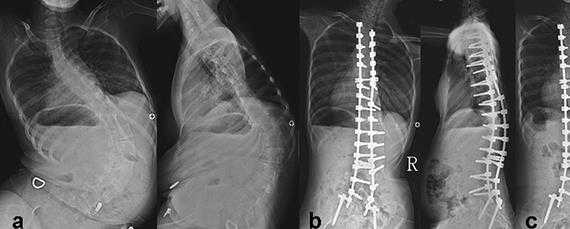

Прогрессирование патологии приводит к возникновению тяжелого сколиоза, что влечет за собой изменение формы грудной клетки и появление трудностей при дыхании. Именно в этом таится главная угроза болезни для жизни.

Хирургическое лечение

Современная медицина способна помочь пациентам с СМА за счет выравнивания позвоночника. Вы можете существенно повысить качество жизни и избавиться от болей с помощью хирургического лечения нейромышечного сколиоза. Наши спинальные хирурги способны грамотно провести операцию с учетом всех особенностей пациента и добиться предельно высоких результатов. Цены наших услуг приведены в прайсе.

Суть хирургического лечения нейромышечного сколиоза заключается в выполнении многоуровневой фиксации позвоночника с помощью специальных конструкций. Это предполагает изменение и закрепление в максимально приближенном к нормальному положению каждого сегмента искривленной части позвоночного столба.

Многоуровневая фиксация реализуется за счет установки многочисленных опорных элементов и выбора в качестве опорных точек крестца и таза и позвонков верхнегрудного отдела. Но часто ее проведение требуется практически по всей длине позвоночника, так как у больных спинальной мышечной атрофией сколиотические деформации достигают предельно тяжелых форм.

Она позволяет не только практически полностью выровнять позвоночник, но и равномерно распределить нагрузку на него, а также надежно удерживать его в новом положении. Благодаря этому больной избавляется от выраженного комфорта во время сидения и лежания, решаются психологические проблемы, спровоцированные выраженной деформацией позвоночного столба. Но главное достоинство операции заключается в устранении негативного влияния сколиоза на легкие и другие внутренние органы.